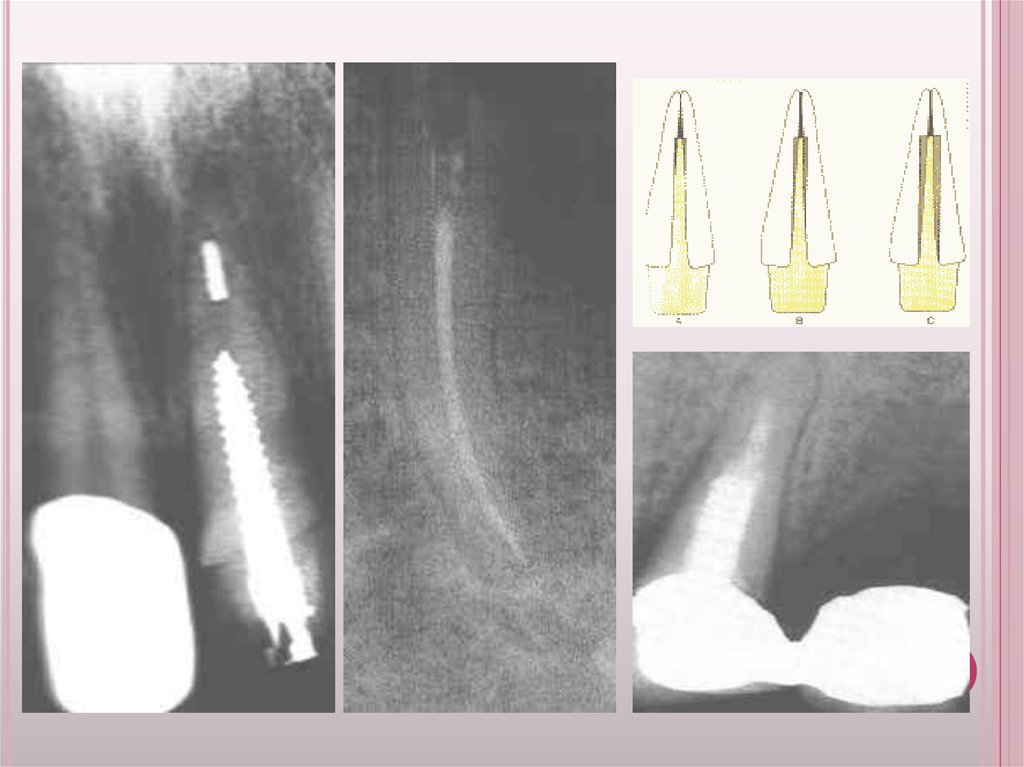

1.Тісті конусты 2.тегіс конусты 3.бұрама конусты 4.тісті цилиндрлі

5.тегіс цилиндрлі 6.Бұрама цилиндрлі

26.

Фабрикадан

шығатын

штифтердің

барлығы конус

немесе цилиндр

тәрізді,кейде

екеуі қосылған

күйде

28. Конусты штифтке қарағанда цилиндрлі штифтің ретенциясы жоғары Цементке отырғызып жатқанда конусты штифтер цилиндрлі штифтерге

КОНУСТЫ ШТИФТКЕ ҚАРАҒАНДА ЦИЛИНДРЛІ ШТИФТІҢ

РЕТЕНЦИЯСЫ ЖОҒАРЫ ЦЕМЕНТКЕ ОТЫРҒЫЗЫП ЖАТҚАНДА

КОНУСТЫ ШТИФТЕР ЦИЛИНДРЛІ ШТИФТЕРГЕ ҚАРАҒАНДА

ҚЫСЫМЫ АЗ. ФУНКЦИОНАЛДІ КҮШ ТҮСКЕНДЕ КЕРІСІНШЕ,

ЯҒНИ СОДАН ТҮБІР СЫНЫП КЕТУІ МҮМКІН.

29. Цилиндрический штифт с зубчатой поверхностью и с продольной канавкой.

ЦИЛИНДРИЧЕСКИЙ ШТИФТ С ЗУБЧАТОЙ

ПОВЕРХНОСТЬЮ И С ПРОДОЛЬНОЙ КАНАВКОЙ.